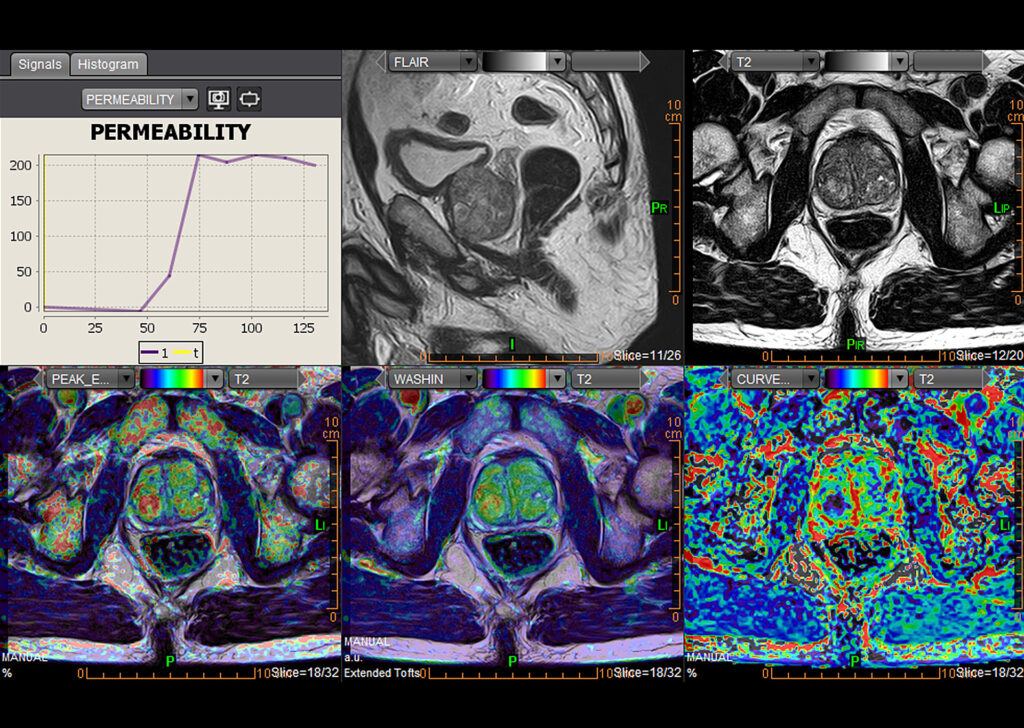

MR Body Full

MR Head and Neck, MR Breast, MR Prostate, MR Rectum, MR MSK, MR Female Pelvis, Advanced Multiparametric Analysis, Dynamic Contrast Enhanced Permeability, Diffusion Weighted Imaging, Kinetics, Longitudinal Analysis, Intravoxel Incoherent Motion, Metabolic, and Onco-Inflammatory.

MR Female Pelvis

Olea MR Female Pelvis application is integrated into Vitrea Advanced Visualization and provides efficient analyzation of morphological changes in the pelvic area under pathological conditions.

MR Rectum

Olea MR Rectum application workflow offers efficient multi-step assisted post-processing and 3D visualization for rectal pathologies.